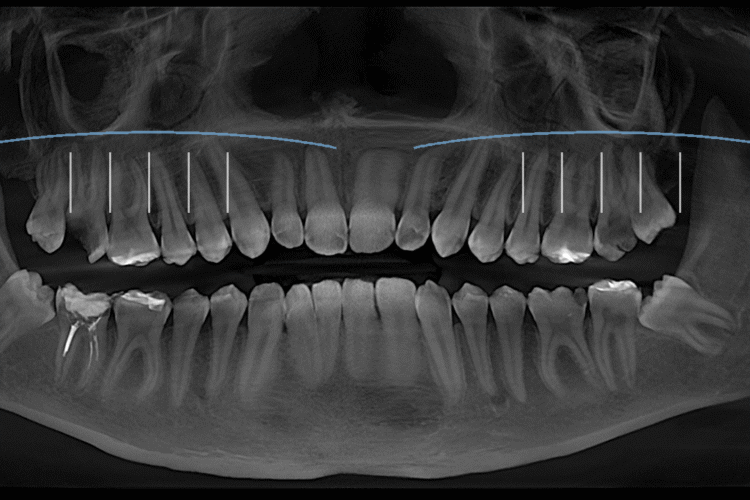

Верхньощелепні (гайморові) пазухи розташовані безпосередньо над коренями верхніх жувальних зубів — молярів і премолярів. У частини людей між коренями зубів і пазухою є лише тонкий кістковий прошарок, а інколи верхівки коренів анатомічно дуже близькі до порожнини пазухи. Саме через цю близькість будь-які запальні процеси в носі й пазухах можуть віддавати в зуби.

Під час ГРВІ слизова оболонка носа та пазух набрякає, порушується вентиляція, у пазухах накопичується слиз або запальний ексудат. У результаті зростає внутрішній тиск. Цей тиск передається на прилеглі тканини та нервові структури, які іннервують верхні зуби. У відповідь людина відчуває зубний біль, хоча самі зуби при цьому можуть бути анатомічно й стоматологічно здоровими.